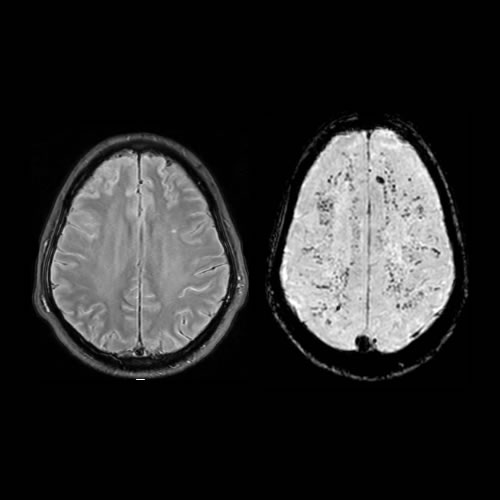

Noviembre 2023. Sanatorio Allende Paciente que consulta por cefalea occipital, de 12 hs de evolución, acompañado de vómitos alimenticios, fotofobia y fiebre